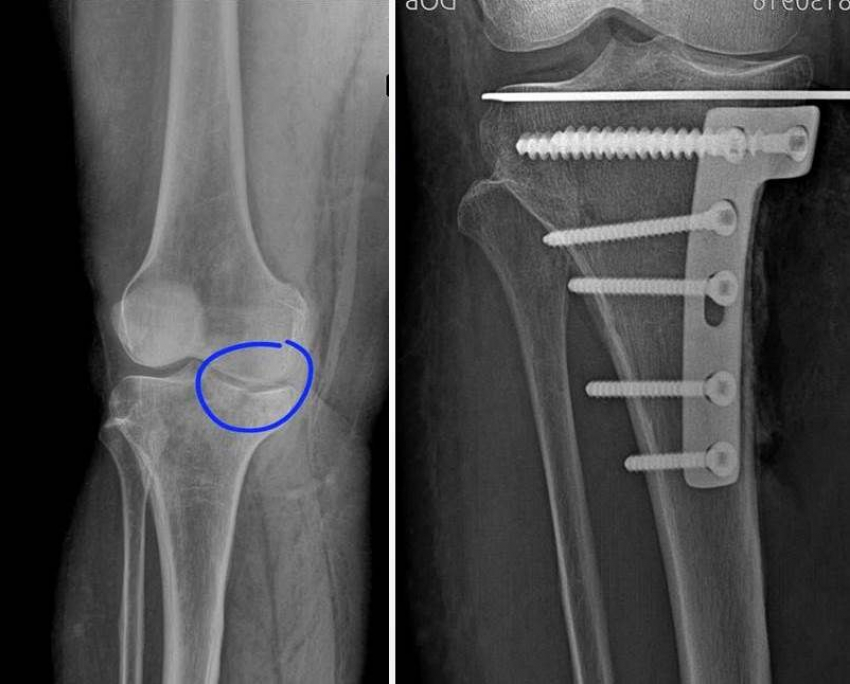

У пациентки диагностировали оскольчатый компрессионный перелом медиального мыщелка левой большеберцовой кости со смещением отломков и кровоизлияние в полость левого коленного сустава.

«Специалистами было принято решение о применении не используемого ранее в больнице способа остеосинтеза внутрисуставных компрессионных переломов под контролем артроскопии», - рассказали в региональном минздраве.

Без вскрытия суставов медики сопоставили отломки и зафиксировали их спицей, а далее – опорной титановой платиной и винтами.